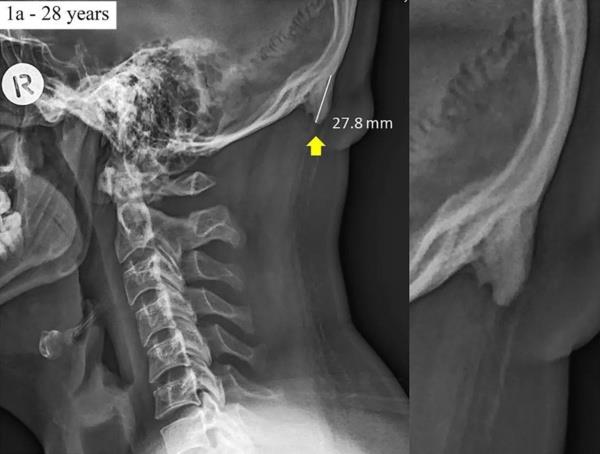

2. Avustralya’daki Sunshine Coast Üniversitesi’den bilim adamları Dr. David Shahar ve Prof. Mark Sayers, 18-30 yaş arasındaki 218 kişinin röntgen çekimlerini inceledi. Yapılan araştırmalar sonucu röntgen çekilen kişilerin neredeyse yarısının kafatası şeklinin yoğun cep telefonu ve tablet kullanımına bağlı olarak ‘değiştiği’, boynuzumsu bir çıkıntıya benzediği belirtildi.

Avustralya’daki Sunshine Coast Üniversitesi’den bilim adamları Dr. David Shahar ve Prof. Mark Sayers, 18-30 yaş arasındaki 218 kişinin röntgen çekimlerini inceledi. Yapılan araştırmalar sonucu röntgen çekilen kişilerin neredeyse yarısının kafatası şeklinin yoğun cep telefonu ve tablet kullanımına bağlı olarak ‘değiştiği’, boynuzumsu bir çıkıntıya benzediği belirtildi.

3. Yapılan araştırmaya göre, gününün büyük kısmında teknolojik aletlere kafasını eğerek bakan gençlerin, kafatasındaki oksipital kemik denen bölge, görünür şekilde belirginleşmeye başlıyor.

Yapılan araştırmaya göre, gününün büyük kısmında teknolojik aletlere kafasını eğerek bakan gençlerin, kafatasındaki oksipital kemik denen bölge, görünür şekilde belirginleşmeye başlıyor.

6. Ensenin üstünde sivrilen 10-30 milimetre arasında değişen çıkıntıya, &#8216;dış oksipital kabartı&#8217; deniyor. Dış oksipital kabartıya, taşınabilir dijital cihazlar yaygınlaşmaya başlamadan önce daha çok yaşlı insanlarda rastlandığı, gençlerde ise oldukça nadiren rastlandığı belirtiliyor.

Ensenin üstünde sivrilen 10-30 milimetre arasında değişen çıkıntıya, ‘dış oksipital kabartı’ deniyor. Dış oksipital kabartıya, taşınabilir dijital cihazlar yaygınlaşmaya başlamadan önce daha çok yaşlı insanlarda rastlandığı, gençlerde ise oldukça nadiren rastlandığı belirtiliyor.